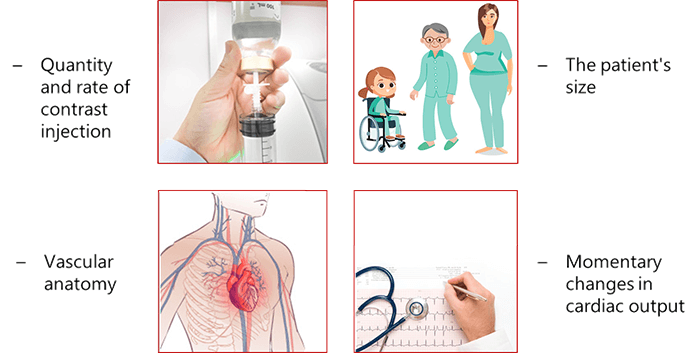

The arterial input function is influenced by the quantity and rate on the contrast injected for the patient, patient size (Child, man and woman), vascular anatomy and the momentary changes in cardiac output.